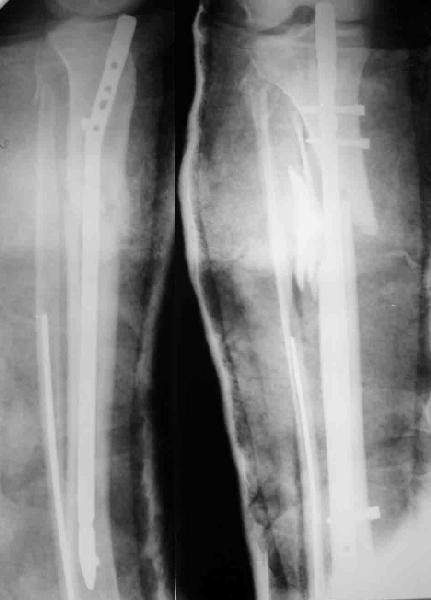

Вчера поступила к нам в отделение. Клинически определяется приличная подвижность, градусов 35 в переднезаднем направлении. На снимках еще видны фиксированная тоникм стержнем уже сросшаяся малоберцовая кость, и тоже сросшийя перелом дистального метадиафиза большеберцовой костибез признаков хирургической фиксации (?). Сегодняшний снимок также в приложении.

Планируем удаление пластинки и закрытый интрамедуллярный остеосинтез с рассверливанием.

Что скажете, коллеги? Что можно/нужно было сделать, чтобы избежать сегодняшней проблемы? Есть ли другие предложения по нынешнему плану?